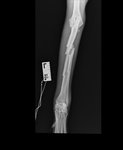

Er ist eine sie. Eine an sich stolze, schöne Windhündin. Leider aber schon bevor sie verunfallte  in erbärmlichem Zustand, abgemagert, voller Parasiten und Narben. Schon auf den ersten Blick ist eine offene Fraktur des Vorderbeins zu erkennen. Eine genauere Untersuchung ergibt, dass sie sich darüber hinaus aber, Gott sei Dank, keine lebensbedrohlichen Verletzungen zugezogen hat. Wir nehmen sie also mit zu uns und stabilisieren ihren Zustand.

Wir organisieren also den Transport ins drei Stunden entfernte Bukarest. Ab dann liegt die Verantwortung in anderen Händen. Ich muss vielleicht erwähnen, dass Windhunde, was Frakturen angeht, aufgrund ihrer anatomischen Besonderheiten, keine dankbaren Patienten sind. Ist eine Fraktur offen, verschlechtert das die Prognose zusätzlich. Und Mangalas Bein war zudem mehrfach gebrochen.

Schließlich die erleichterde Nachricht, dass die Operation erfolgreich verlaufen ist. Es war jedoch eine sehr lange und aufwändige Operation und da mit Wundheilungsstörungen zu rechnen ist, soll Mangala noch etwas länger in der Klinik bleiben. Aus ein paar Tagen, werden schließlich vier Wochen. Vier Wochen, in denen die Ärzte und Mitarbeiter der Klinik sich liebevoll um sie kümmern und uns auf dem Laufenden halten. Stets bekommen wir zu hören, was Mangala für eine tolle Patientin und überhaupt ein wunderbarer Hund sei.

Ihr Bein heilt zufriedenstellend. Es wird immer etwas ein Thema bleiben in ihrem Leben. Doch da sie kein übertrieben lebendiger Hund ist, wird sie gut damit zurechtkommen.